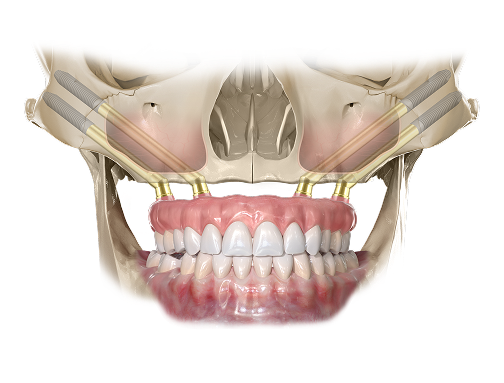

Bazuje ona na wszczepieniu czterech precyzyjnie rozmieszczonych implantów tytanowych, stanowiących solidne oparcie dla stałych prac protetycznych, takich jak mosty, lub dla protez ruchomych wspartych na implantach.

W przypadkach ograniczonej ilości kości w górnym łuku zębowym istnieje możliwość zastosowania implantów jarzmowych Zygoma. Te dłuższe wszczepy są zakotwiczane w kości jarzmowej, co zapewnia ich wyjątkową stabilność oraz pozwala na uniknięcie rozległych zabiegów rekonstrukcji kostnej. Rozwiązanie to sprawdza się zwłaszcza w sytuacjach, gdy tradycyjne implanty nie są możliwe do zastosowania. Nasz gabinet specjalizuje się w tej metodzie od 2000 roku.

Poprzez użycie pochylonych implantów w odcinkach bocznych pozwala uniknąć uszkodzenia ważnych szczegółów anatomii oraz zwiększa powierzchnię przylegania i przez to wzmacniaosteointegrację implantów z kością. Redukuje ilość implantów niezbędnych do pełnołukowej rehabilitacji bezzębia.